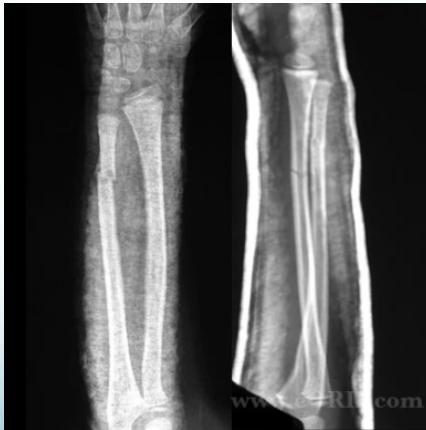

Intramedullary Elastic Nail

- 2 fractures at the same level = 100% unstable

- When unstable or re-displaces in cast